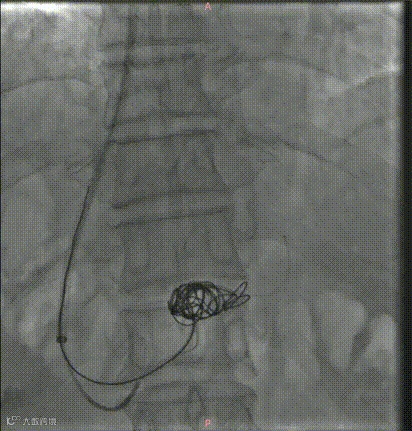

超选择插入至曲张静脉,注入弹簧圈栓塞

超选择插入至曲张静脉,经微导管注入格鲁巴胶至曲张静脉血流基本停滞

术后造影(即刻效果):曲张静脉血管网未见显影